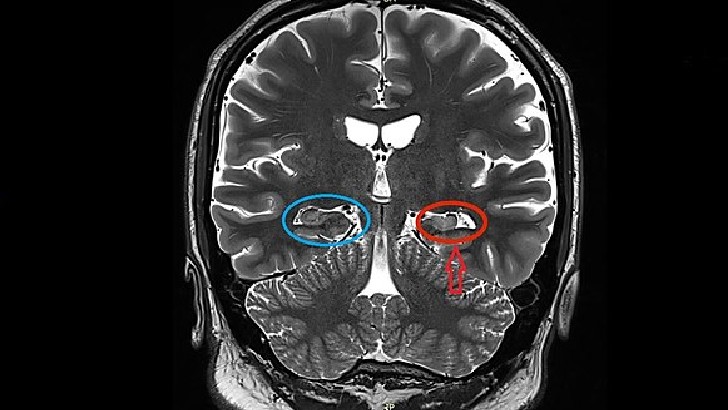

What causes multiple sclerosis symptoms?

Degeneration of the sheath that covers the neurons of the central system and the replacement of this sheath with scar tissue.